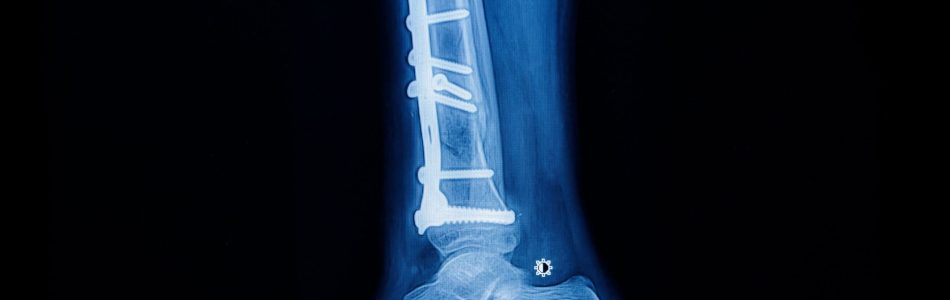

taitanium implant screws

This is a question that is often asked, especially in the revision or trauma setting. Titanium screws have been used successfully for many years, becoming the gold standard for implant fixation. The issue with titanium is that its durability depends on its microstructure and surface properties. Titanium is very reactive and will change its structure over time to environmental changes.

For example, titanium screws placed in the bone will rapidly become coated with calcium and phosphate. This increases the surface area of the screw, which improves its fixation. However, this coating is susceptible to corrosion and does not protect the bone from decay. The corrosion process can cause the bone to dissolve, leading to screw loosening or failure.

titanium impant screws

When placed in the bone, titanium screws will undergo a transformation process known as the surface oxide layer (SLOR). A layer of oxide forms on the surface of the screw, resulting in the formation of a titanium oxide layer. This layer protects the screw from further corrosion. Over time, the SLOR will gradually be lost, resulting in corrosion of the screw.

The length of time the screw remains in the SLOR depends on its environment. The environment that the screw is placed in can be divided into three different phases. The first phase is the integration phase, which lasts between 1- 3 months. During this time, the screw is fully surrounded by bone. This phase is crucial for screw fixation, as any micromotion of the screw in this period can lead to screw loosening. The second phase is the remodeling phase. This is when the screw is surrounded by an interfacial layer formed from the body fluids.

This layer is responsible for further transformation of the screw. The final phase is the degradation phase. When placing the screw in the bone, it is surrounded by bone. However, the bone is gradually dissolved over time, and the screw becomes exposed to the surrounding environment. Below is a chart outlining how titanium screws respond to different loads and how long they remain in the SLOR. For example, if a titanium screw is placed in a femur and subjected to 50kg, it will remain in the SLOR for approximately five years. However, if the same screw is placed in a femur and subjected to 75kg, it will only remain in the SLOR for about one year.